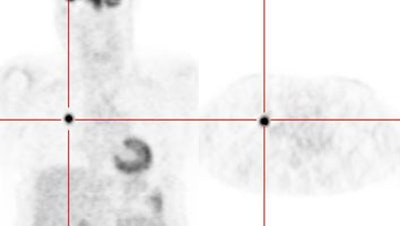

Lung cancer 1 cm lesion: The images below were from a patient with a 1 cm sized right upper lobe lung cancer. Note the excellent conspicuity of the lesion on FDG PET imaging. The exam was acquired using an ECAT EXACT PET scanner (CTI) with 5 min/bed emission and 2 min/bed segmented transmission. OS-EM iterative reconstruction was used for exam reconstruction. Case courtesy of Mallinckrodt Institute of Radiology/ Barnes Hospital, St. Louis and CTI PET Systems, Inc. |